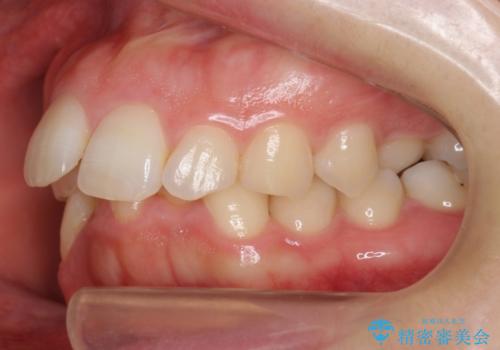

- 前歯のがたがたと出っ歯を主訴に来院。

CTを撮影したところ、臼歯部の頬側の骨の厚みが非常に大きく、通常では考えられない量の歯列の拡大が可能でした。

今回は健康を損なわずに非抜歯で治療が可能でしたが、

歯ぐきや骨の厚みが薄い他の患者さんでは難しいです。

左上5は180度捻転していましたので、そのまま並べています。

遠心移動などは行わず、IPRと拡大のみで治療を行いました。

一般的に非抜歯矯正を無理に行うと、口元がモッコリ出てしまうことがあります。しかし、今回は前歯を前に出さないような設定にしており、口元が出ることもありませんでした。